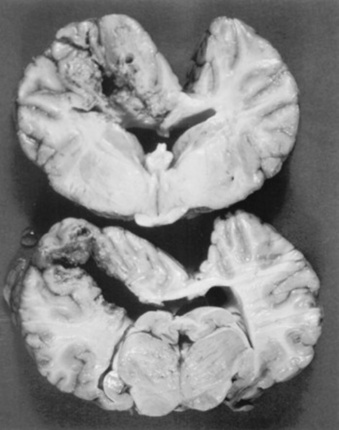

Pathology

The major pathologic features in the central nervous system (CNS) result from the vascular damage caused by fumonisin toxins, including liquefactive necrosis and degeneration or malacia of the white matter of one or both cerebral hemispheres.1347,1348 The size of the lesions may vary from 0.5 cm in diameter to complete necrosis of the entire cerebral cortex.1331 Flattening of the cortical gyri, enlargement of the cerebral cortex, vascular congestion, cortical softening, yellowish discoloration of the white matter, hemorrhage, and cavitation of the cerebral cortex may be present1331,1338,1340 (Fig. 35-14). A gelatinous fluid can be seen in many of the cavitary lesions.1338 Hemorrhage in the CNS also has been reported.1343 Lesions in the visceral organs, including hepatic congestion, centrilobular hepatic necrosis, hemorrhagic enteritis, and cystitis are found in some horses. The relationship between these lesions in the CNS and those in the liver, urinary bladder, and GI tract is unknown.

Fig. 35-14 Characteristic appearance of a malacic lesion in the brain of a horse that died of moldy corn poisoning.

Courtesy Dr. R.H. Whitlock.